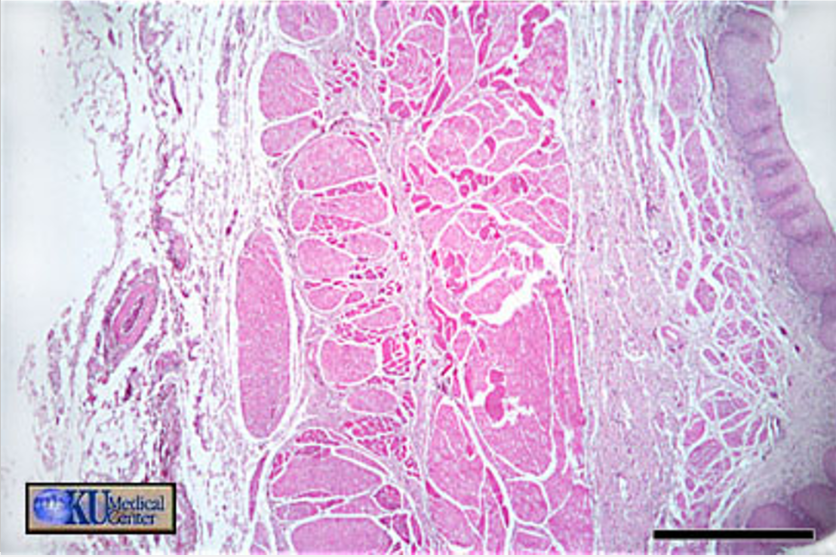

thick skin

green

epidermis

yellow

dermis

red

hypo dermis